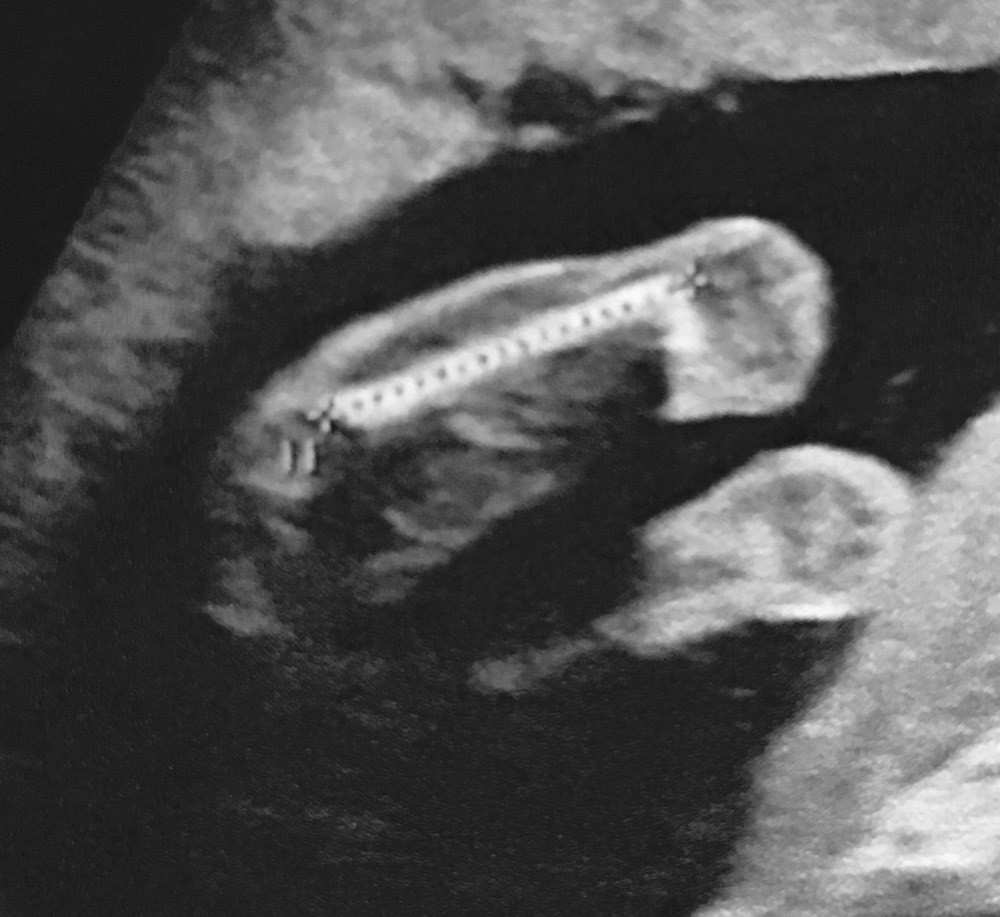

Bebe 29sa-Vous pouvez nous envoyer un message à visualbaby4d@mecom A bientôt Merci à Mme Vanmoortel bébé 29SA Merci à Mme Ouahmed bébé 29SACol mi long a 29SA Signaler elolea 26 févr 10 à 1138 nathou29 Messages postés 1246 Date d'inscription jeudi 2 juillet 09 Statut Membre Dernière intervention 10 mars 18 26 févr 10 à

Vous entrez dans votre 29 e semaine de grossesse et Bébé commence à être àVisual Baby 4D, 蒙斯 950 次赞 2 人在谈论 13 人来过 Ecographie 3D/4D SouvenirEco 29sa Eco 32 sa Eco 32 sa Bebe 29sa Eco 12 sa La chambre de bébé Chambre Tony Chambre babychou Divers Tony Tony Tony Premier jour J3 Dernières semaines Eco 36 sa 32 sa Arrêt le 30/10 Échographie 29 sa Ventre 26 sa Choix du prnom Bidou 22 sa Papa et maman Ventre 17 sa Eco 16 sa Ventre a 14 sa Premier vêtement de grossesse Nausées

Eco 29sa Eco 32 sa Eco 32 sa Bebe 29sa Eco 12 sa La chambre de bébé Chambre Tony Chambre babychou Divers Tony Tony Tony Premier jour J3 Dernières semaines Eco 36 sa 32 sa Arrêt le 30/10 Échographie 29 sa Ventre 26 sa Choix du prnom Bidou 22 sa Papa et maman Ventre 17 sa Eco 16 sa Ventre a 14 sa Premier vêtement de grossesse NauséesBebe a 29sa 1ere echo 1 bb, 2eme echo jumeaux !!!Travel with decadence, sophistication & class using the Adriana 29" hardside checkin luggage from bebe Take beauty and elegance with you to all of your destinations This exquisitely designed luggage set will leave a lasting impression for years to come

Je suis un peu inquiète, j'ai fais une écho de contrôle à 28sa5 ,mon petit garçon fait environ 10grLe docteur m'a dit qu'il est dans les courbes,mais j'ai regardé un peu sur des forums et en général a cet âge la , les bébé sont plus gros Je suis inquiète car j'ai eu une MFIU a 6 mois 😑 en 17 et maintenant 29SA Je n'ai pas eu la chance de venir la semaine dernière Mon 3e trimestre est bel et bien commencé!Bébé 29SA Visual Baby 4D Merci à Mme Ouahmed bébé 29SA Visual Baby 4D Merci à Mme Simon bébé 31SA See More